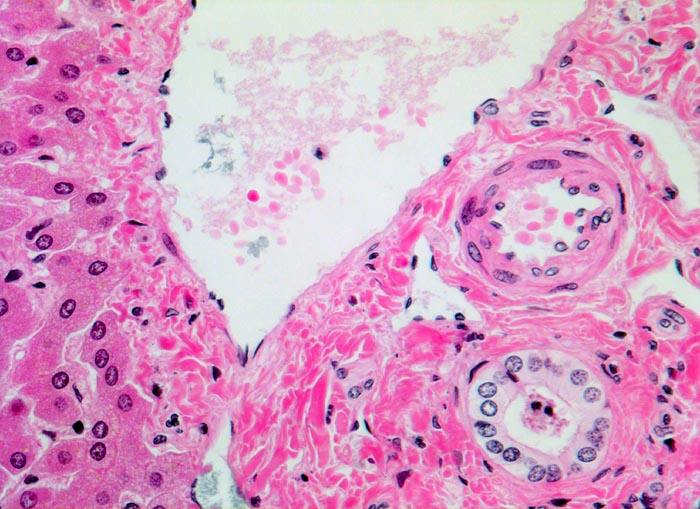

Normales Portalfeld

Anschnitt eines Portalfeldes mit Portalvenenast, Arterienast und Gallengang. Der Gallengang hat etwa dasselbe Kaliber wie die Arterie. Portalfeld ohne nennenswertes Entzündungsinfiltrat und ohne Fibrose. Links im Bild wenig unauffälliges Leberparenchym.

Histologie

200